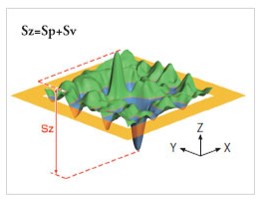

Vous pouvez également réaliser des acquisitions en 3D de la surface de la peau. Grâce à une technique appelée stéréo photométrique, le système C-Cube analyse plusieurs images dans différentes conditions d’éclairage. Le logiciel estime les normales de surface. Combiné à une calibration géométrique, il produit des informations d’élévation à chaque pixel.

Grâce à sa capacité unique de mesure de paramètres 3D, il est possible de mesurer l’élévation des boutons avec la hauteur du pic (Sp) et l’amplitude totale (Sz). Un effet du produit testé pourra être prouvé si l’élévation du pic diminue dans le temps.

Élévation des boutons Hauteur des pics et amplitude